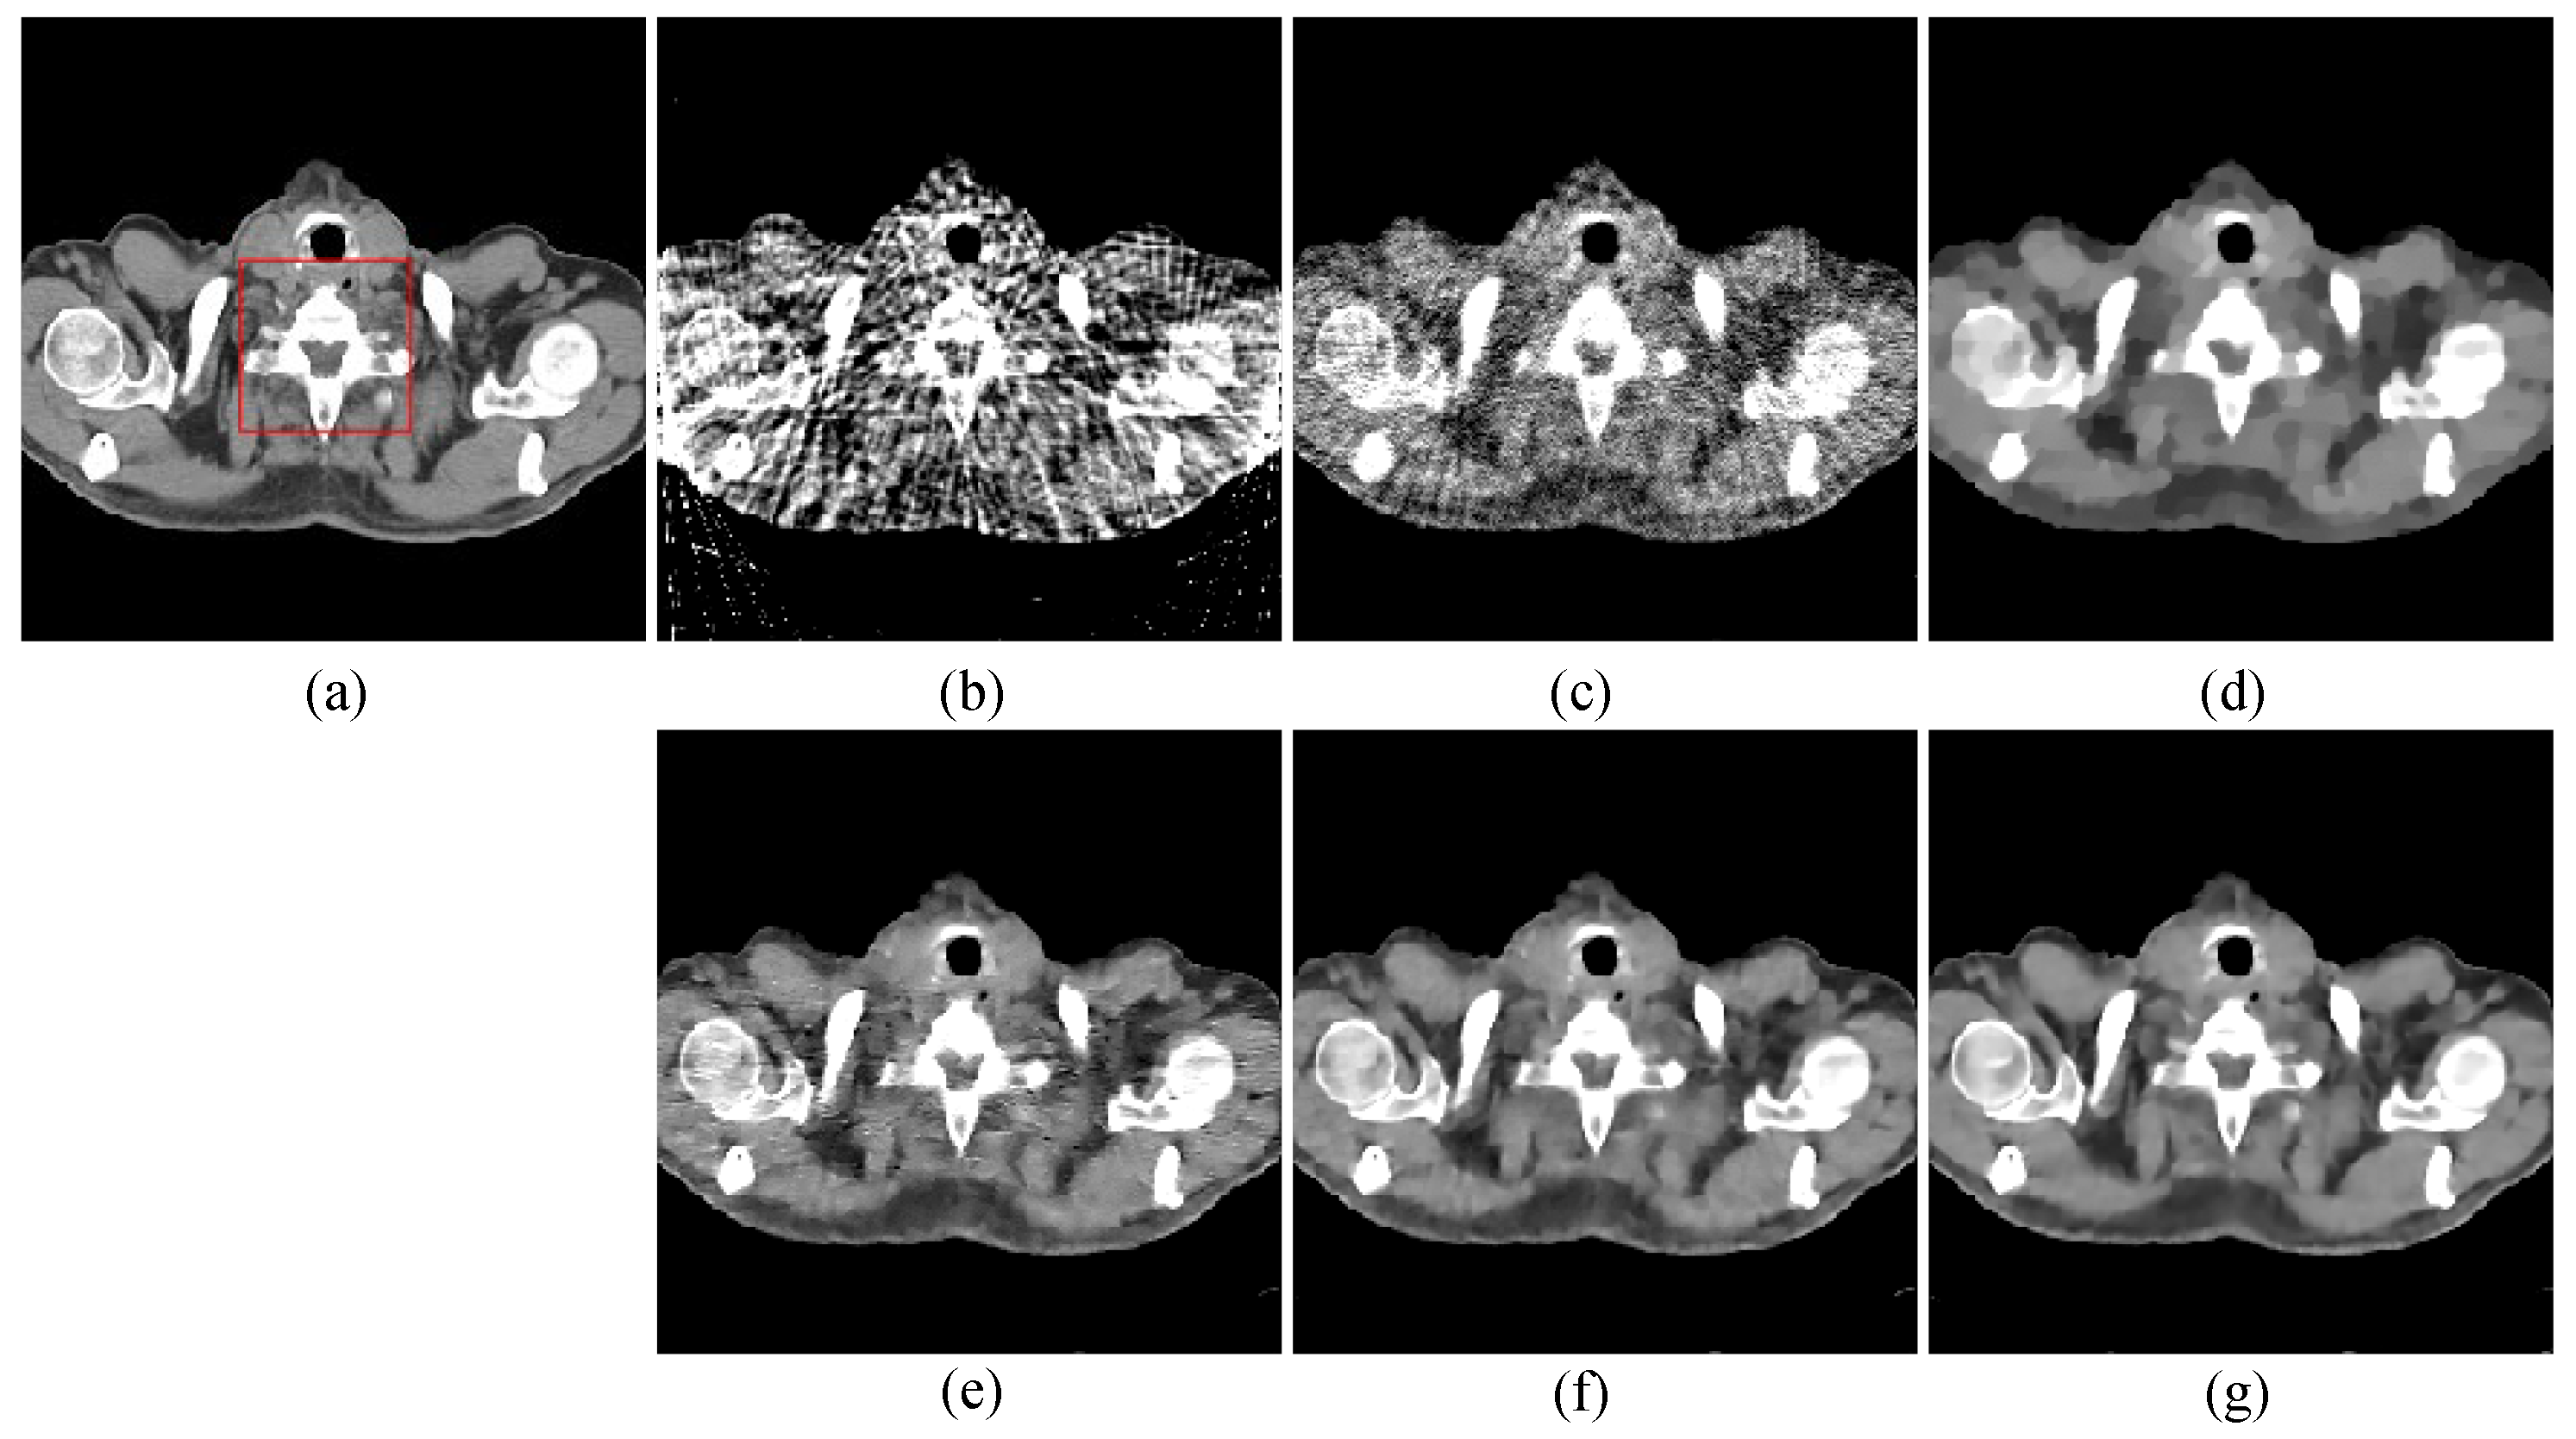

The second image reconstruction experiment is conducted on an abdomen image with more image details to show the feasibility of our algorithm for SVCT reconstruction, as shown in Figure 9. We extracted 80, 64, and 48 views from a full scan and set the parameters as follows: a = 0.5, γ1 = 0.1, and γ2 = 0.06. The reconstructed results using different algorithms are shown in Figure 10, Figure 11 and Figure 12. As can be seen from the figures, our algorithm performs better than other algorithms in preserving small structures and reducing noise. Specifically, FBP reconstruction results contain severe artifacts as displayed in Figure 10b, Figure 11b and Figure 12b. OS-SART reconstruction results also have obvious noise as displayed in Figure 10c, Figure 11c and Figure 12c. TV has a better performance than FBP and OS-SART, but the result has blocky artifacts, as displayed in Figure 10d, Figure 11d and Figure 12d. The PICCS and TVPI-G algorithms have an improvement in image quality, but fine image structures are losing detail and some edge information is blurring, as displayed in Figure 10e,f, Figure 11e,f and Figure 12e,f. As can be observed from Figure 10g, Figure 11g and Figure 12g, the proposed algorithm performs better not only in preserving edge and image details, but also in reducing noise.

Figure 11. 64-views reconstruction results of abdomen image: (a) ground truth, (b) FBP, (c) OS-SART, (d) TV, (e) PICCS, (f) TVPI-G, and (g) NPICCS. The display window is [−150 250] HU.

Applsci 13 10320 g011

Figure 12. 80-views reconstruction results of abdomen image: (a) ground truth, (b) FBP, (c) OS-SART, (d) TV, (e) PICCS, (f) TVPI-G, and (g) NPICCS. The display window is [−150 250] HU.

Applsci 13 10320 g012